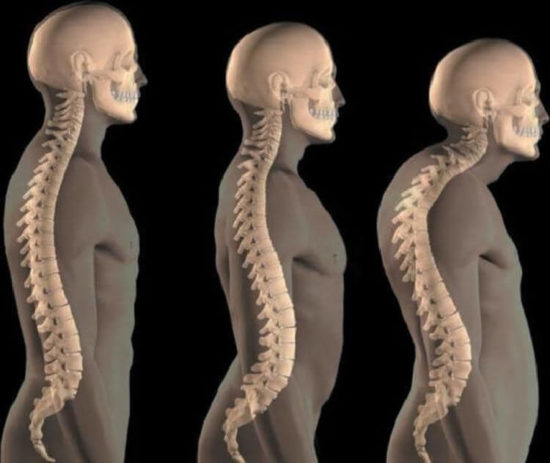

Структура позвоночника: сегменты и тазовые отделы в фотографиях